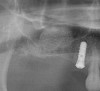

Figure 17  Preoperative radiograph showing ridge resorption.

Figure 17